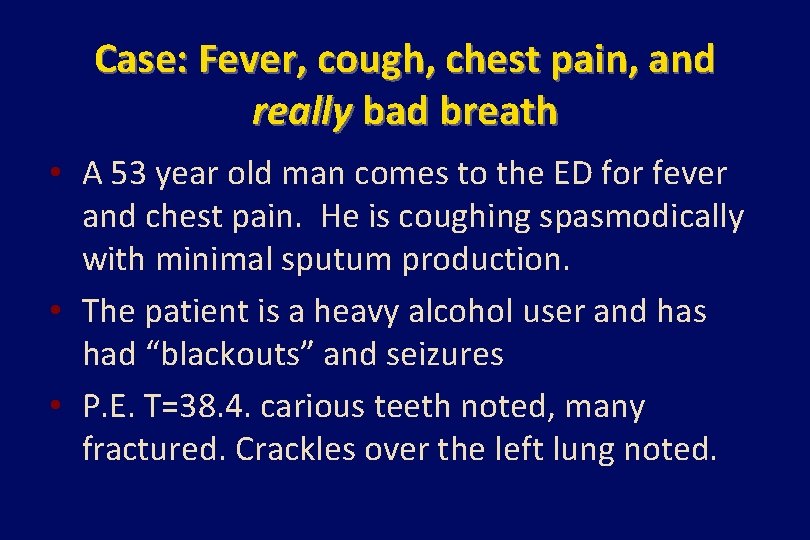

Case: Fever, cough, chest pain, and really bad breath • A 53 year old man comes to the ED for fever and chest pain. He is coughing spasmodically with minimal sputum production. • The patient is a heavy alcohol user and has had “blackouts” and seizures • P. E. T=38. 4. carious teeth noted, many fractured. Crackles over the left lung noted.

Case (continued) • He is admitted and started on ceftriaxone for probably pneumonia • Later the same night, the patient starts coughing copious amounts of grayish, putrid sputum that can be detected on the next ward. • A chest xray is taken, and treatment with metronidazole is added.